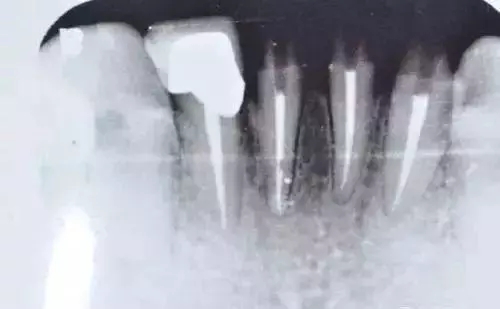

刘小姐的烤瓷牙在使用了六年之后,虽然仍能够正常饮食,但却一直断断续续出现牙痛的症状,靠吃着消炎药来缓解疼痛。直到前不久,刘小姐发现左边上排的烤瓷牙出现松动,于是才到医院进行检查。经过检查发现,她的牙冠内存在的基牙都已经全部发炎,并开始腐烂,只能拔除剩余的腐烂基牙,做全口固定的种植牙。

目前,种植牙对于其他修复方式来说,的确是一个长久有效的修复方式,相比于活动假牙和固定桥修复,不仅不伤害口腔情况,其外观和咀嚼力也都是接近于天然牙,使用时间更是能够达到三四十年。